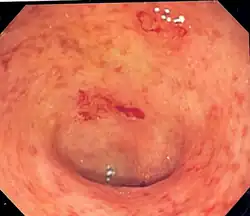

Endoscopic image of a colon affected by ulcerative colitis. The internal surface of the colon is blotchy and broken in places. Mild-moderate disease. | |

Endoscopic

The best test for the diagnosis of ulcerative colitis remains endoscopy, which is the examination of the internal surface of the bowel using a flexible camera. Initially, a flexible sigmoidoscopy may be completed to establish the diagnosis.[73] The physician may elect to limit the extent of the initial exam if severe colitis is encountered to minimize the risk of perforation of the colon. However, a complete colonoscopy with entry into the terminal ileum should be performed to rule out Crohn's disease and assess the extent and severity of the disease.[73] Endoscopic findings in ulcerative colitis include: erythema (redness of the mucosa), friability of the mucosa, superficial ulceration, and loss of the vascular appearance of the colon. When present, ulcerations may be confluent. Pseudopolyps may be observed.[74]

Ulcerative colitis is usually continuous from the rectum, with the rectum almost universally involved. Perianal disease is rare. The degree of involvement endoscopically ranges from proctitis (rectal inflammation) to left-sided colitis (extending to the descending colon) to extensive colitis (extending proximal to the descending colon).[14]